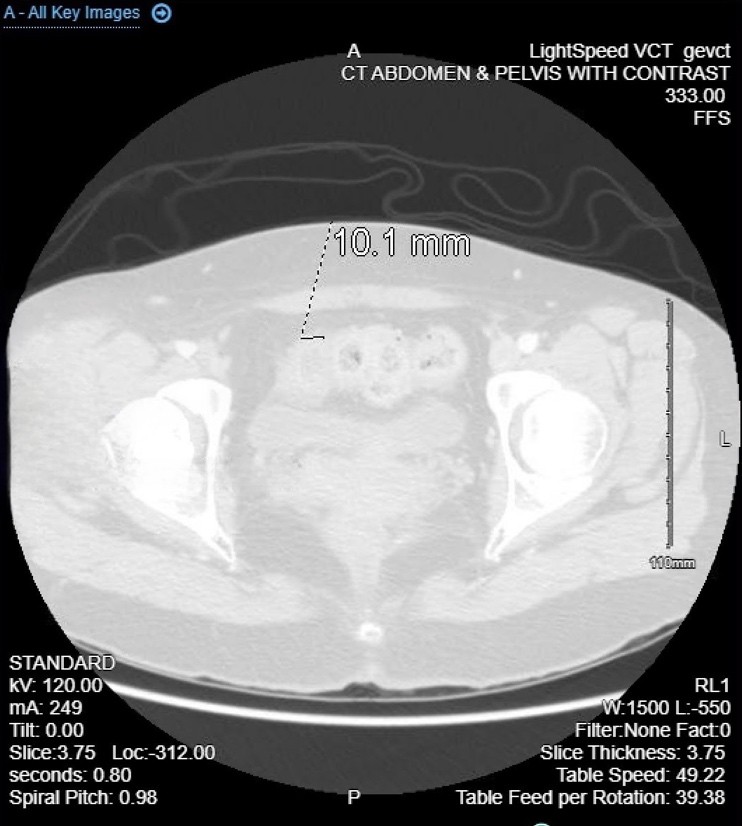

CT imaging showed sigmoid colon wall thickening, a 2.0 × 1.6 × 1.0 cm intramural abscess, and free adnexal fluid, raising suspicion for colitis or inflammatory bowel disease with possible gynecologic etiology.

A 35-year-old woman with a history of dysmenorrhea and chronic constipation presented with acute abdominal pain to ED . Her symptoms on presentation diffuse abdominal pain, nausea, vomiting, diarrhea, chills, and bright red blood per rectum. She had a history of alpha thalassemia, dysmenorrhea fo that she was initially on NuvaRing since 2018, later switching to ParagardIUD placed 2024. Patient was complaining for consitpaiton with mild relief from magnesium citrate and prune juice and other OTC medications.  A CT scan of abodmen with conatrast revealed sigmoid colonic wall thickening with small intramural abscess measuring up to 2.0 x 1.6 x1.0 cm., concerning for colitis of infectious or inflammatory origin and  adnexal free fluid, raising the possibility of gynecological pathology. CBC remarkable for mildly low white count of 13.4, CMP was normal.

Fig. 1 Abdominal computed tomography showed irregularly enhanced wall thickening with suspected intrmural abcess measuring up to 2.0 cm of the sigmoid colon (white-black arrow). tranverse view